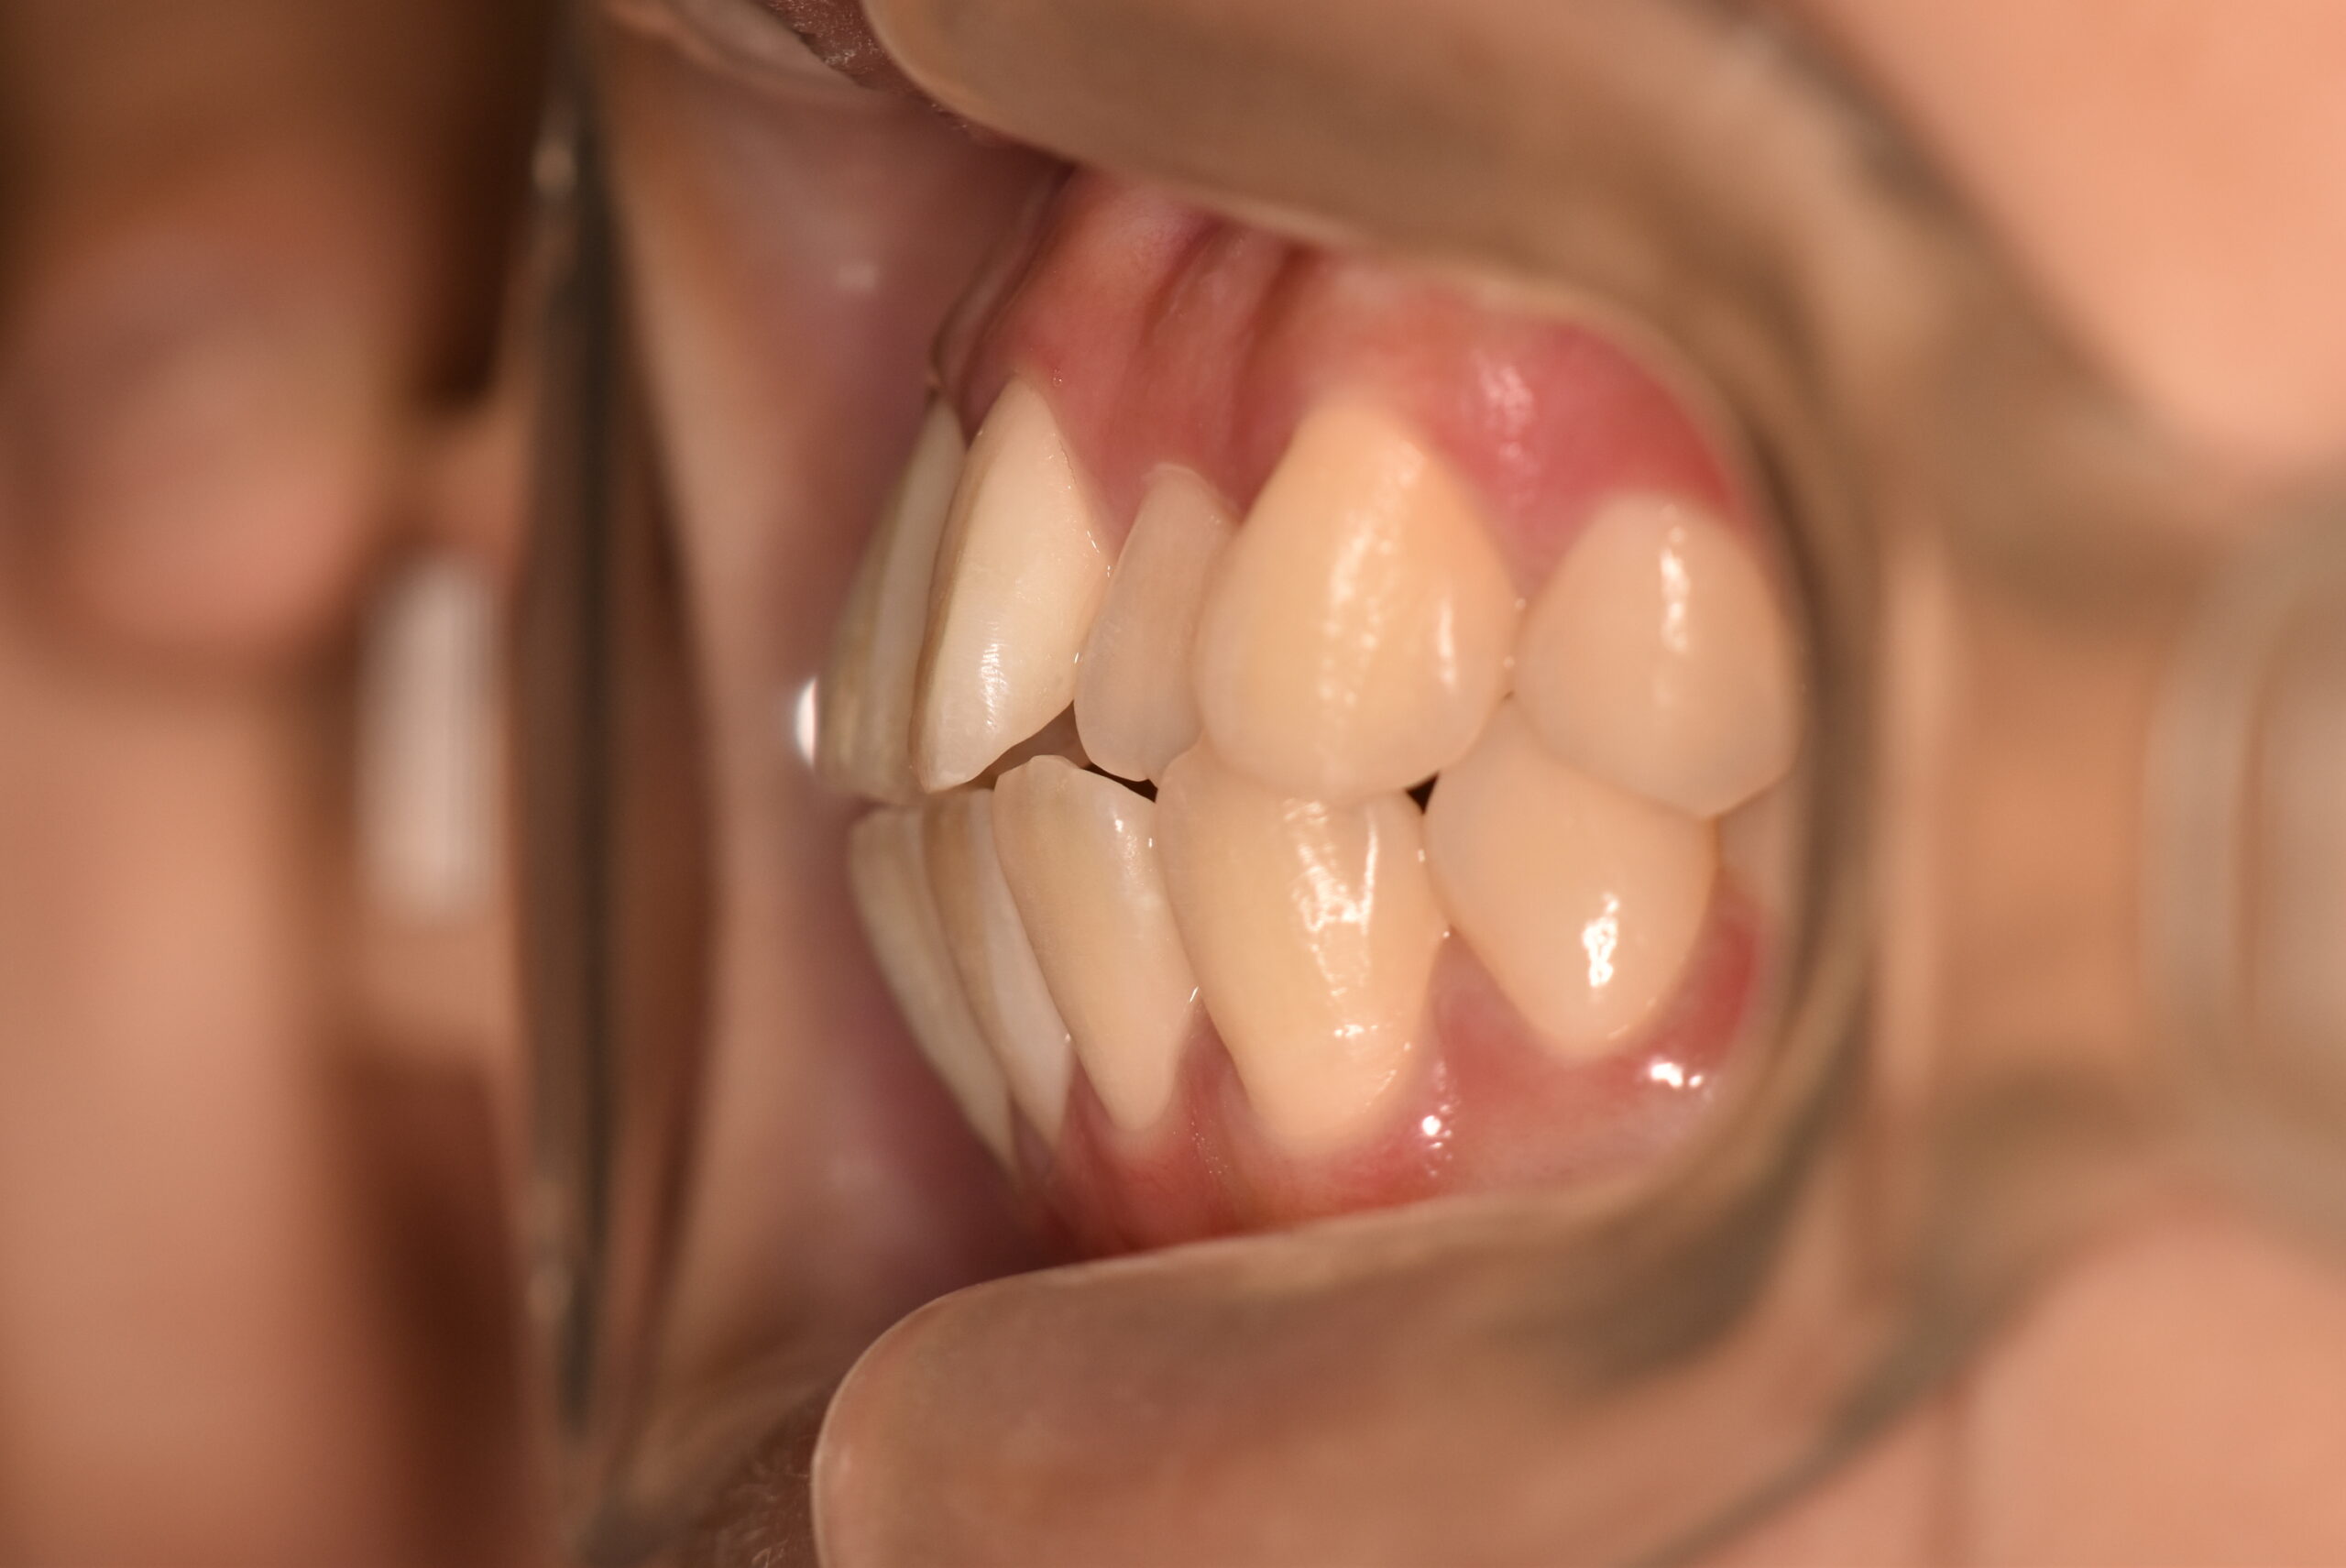

叢生(非抜歯)[2704]

初診時

年齢

17歳11ヶ月 性 別 女性

治療期間 1年10ヶ月 費 用 矯正施術料:900,000円 調整料:5,000円

治療内容の詳細 初診時17歳の女性で、かみ合わせが悪く少しガタガタしていることをを気にされ来院されました。

検査の結果、上下顎叢生を伴うアングル1級不正咬合と診断しました。

治療としては、非抜歯の上、マウスピース型矯正装置(インビザライン)で歯の配列を行いました。

治療期間は、1年10ヶ月でした。